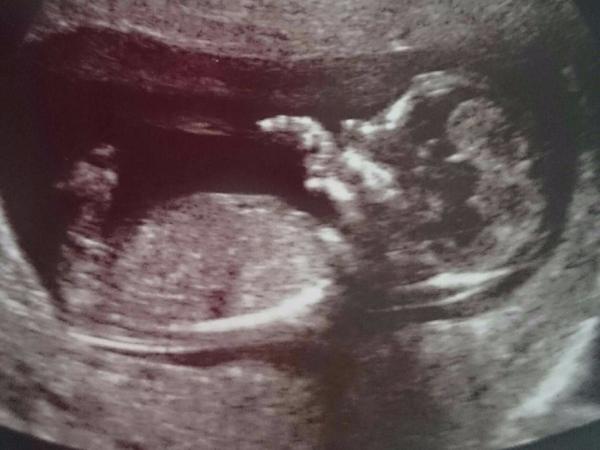

Ahoj maminky a budoucí maminky 😉 Prosím, poradila byste mi některá, co vidíte na fotce z ultrazvuku ve 20. týdnu za pohlaví? Určitě jste foteček viděly už mraky, proto vás žádám o radu...Nechci nikoho ovlivnit, proto svůj tip řeknu později 🙂 Děkuju moc!!!

@matylda123 ja bych tipla kluk,ze vidim mocovou trubici vystupujici ven pindou 🙂